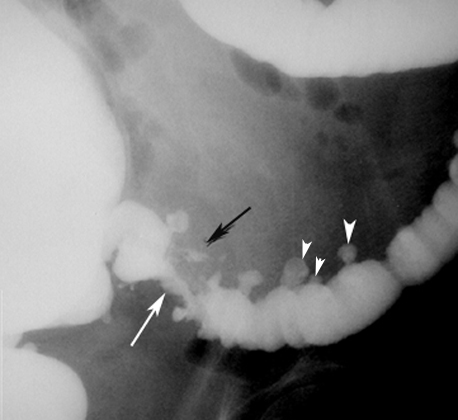

Diverticulitis with Abscess

Findings:

• White arrowheads: Diverticula

• White arrow: Narrowed lumen

• Black arrow: Perforation with intramural abscess